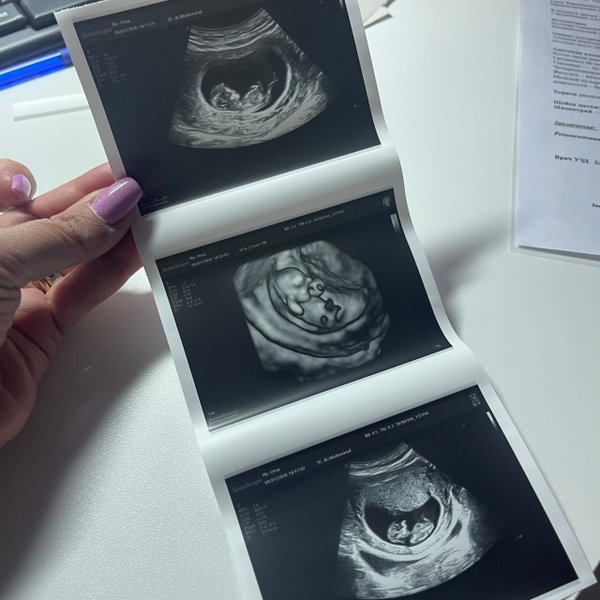

Пятница и суббота⤵️ Запись на УЗИ по телефону ‼️УЗИ всех органов и систем для взрослых и детей с 0 лет --- Бородулина Наталья (Врач УЗИ, Косметология) (13.03.2025): Скоро в Вашем доме появится чудо! . . Загляните в этот милый конверт, чтобы увидеть Ваше маленькое чудо!. #УЗИ_фото Будущие мама и папа в восторге!* ️

Кажется, еще вчера тест показал две полоски, а сегодня мы уже рассматривали ручки и ножки на мониторе ВАШЕ крошечное солнышко‼️ PS.. группа поддержки в виде ️бабушки и мужа на осмотре . были --- Бородулина Наталья (Врач УЗИ, Косметология) (08.01.2026): Давайте поиграем‼️ Угадайте по фото #УЗИ, кто тут ( Шутка, конечно, рано еще Но верить в чудеса можно уже сейчас). Поделитесь в комментариях своими первыми #фото «горошков», «фасолинок» и «эмбриончиков» устроим галерею самого начала жизни ️

Бородулина Наталья (Врач УЗИ, Косметология) (27.03.2025): #УЗИ беременных: Ваш путь к чуду жизни! Каждый момент ожидания — это удивительное приключение‼️ УЗИ — не только возможность увидеть своего будущего малыша, но и важный шаг в заботе о здоровье вас и вашего ребенка. Что дает УЗИ? — Определение срока #беременности — Мониторинг развития плода — Выявление возможных аномалий — Определение пола ребенка (в некоторых случаях) Преимущества УЗИ: — Безопасно и безболезненно — Позволяет вам увидеть вашего малыша на экране — Возможность записа… — Читать дальше

ть видео или #фото для воспоминаний ️ Не упустите шанс‼️ Запишитесь на УЗИ и подарите себе и вашим близким уникальные эмоции!